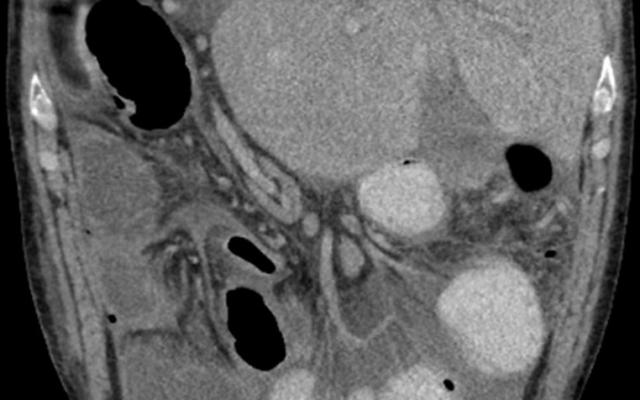

Een 56-jarige man had acute pijn links boven in de buik. Hij was bekend met aanvalsgewijze buikklachten. Een CT-scan van het abdomen toonde, naast een fors gedilateerd colon transversum, ook een congenitale variant van de lever: de rechter en linker leverkwab waren in twee separate delen aanwezig (figuur 1a en 2a). Bij laparotomie waren er aanwijzingen voor een langer bestaande, mogelijk intermitterende torsie van het colon transversum, waarvoor we een transversumresectie met primaire anastomose verrichtten. Tevens legden we een beschermend dubbelloops ileostoma aan. Pathologisch onderzoek toonde geen specifieke afwijkingen. 8 maanden later, 6 dagen na het opheffen…